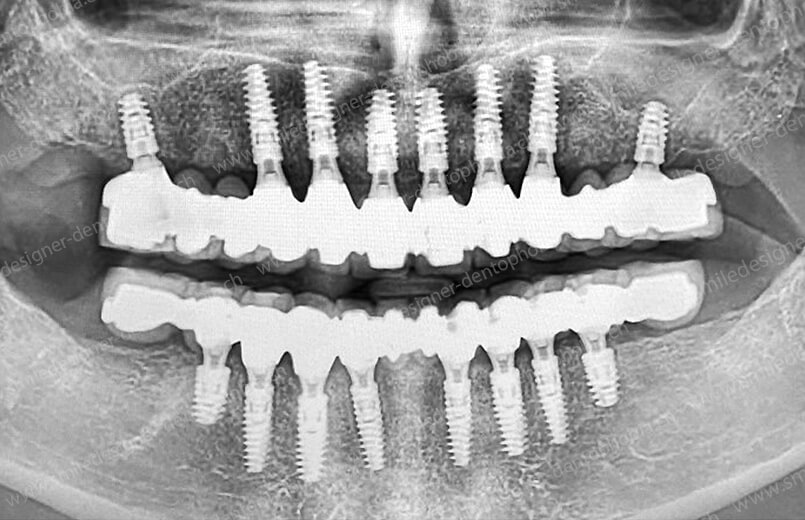

Cas clinique « GOLD STANDARD MCI » bi-maxillaire : Bridge implanto-porté sans extension postérieure (ALL ON 10). Version définitive des bridges avec un cosmétique en céramique.

Cas clinique « GOLD STANDARD MCI » bi-maxillaire : Bridge implanto-porté sans extension (ALL ON 8) au maxillaire et à la mandibule. Version définitive des bridges avec un cosmétique en céramique.

Cas clinique « GOLD STANDARD MCI » maxillaire : Bridge implanto-porté sans extension (ALL ON 8). Version définitive des bridges avec un cosmétique en céramique.

Cas clinique « GOLD STANDARD MCI » maxillaire : Bridge implanto-porté sans extension (ALL ON 10). Version définitive des bridges avec un cosmétique en céramique.

Cas clinique « GOLD STANDARD MCI » bi-maxillaire : Bridge implanto-porté sans extension (ALL ON 10). Version définitive des bridges avec un cosmétique en céramique.

Cas clinique « GOLD STANDARD MCI » bi-maxillaire : Bridge implanto-porté sans extension (ALL ON 8). Version définitive des bridges avec un cosmétique en céramique.